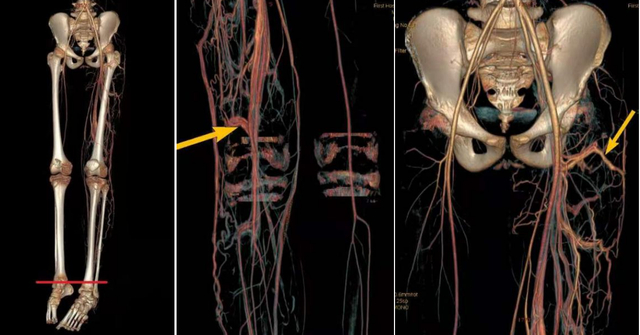

李思医生介绍说,根据病史、症状与体征,初步诊断PW综合征并不困难,但确诊并指导制定治疗方案的最可靠方法是CTA和动脉造影检查。

CTA检查:平片可显示患肢骨骼增长、增粗,骨皮质增厚分层部分病例表现为骨小梁稀疏、 紊乱并伴小囊透亮影软组织肥厚且层次模糊。

动脉造影检查:是诊断本病的主要影像学检查方法,可显示动静脉瘘病变的主要部位、范围以及分流量的大小。

对微小的动静脉瘘常需 行双侧肢体步进动脉造影检查以对照观察患肢的血液动力学异常改变。

动脉造影的主要 X 线征象为:(1)患肢动脉主干增粗血流加快;

(2)动脉分支增多、紊乱、扭曲,常为多发性;

(3)动脉分支的末梢可见毛细血管过早显影染色较深,并可见静脉早期显影现象,但未见直接瘘道。